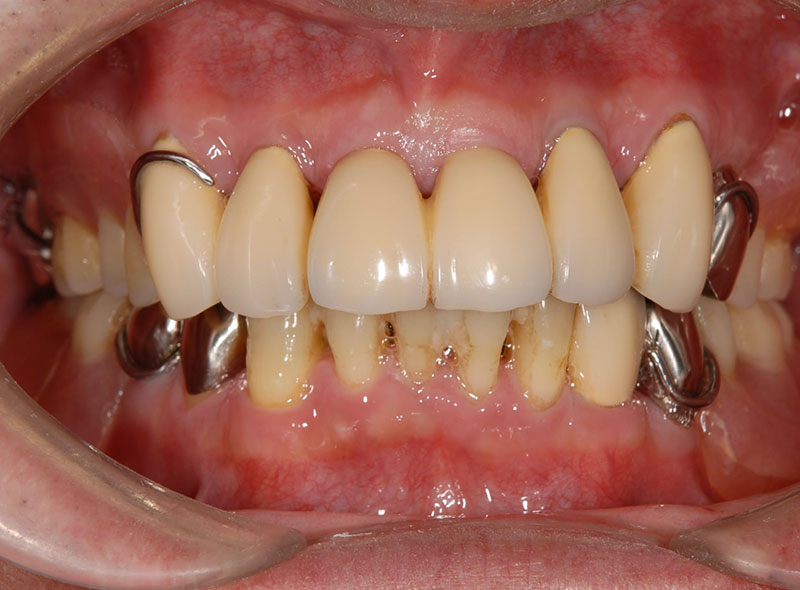

噛み合わせや歯がない場合には、噛み合わせの治療と歯を作る治療も必要になってきます。歯周病の治療は1回で終わることはなく、8回〜10回と長くかかることもあります。

悪くなってから治療を繰り返していると、歯周病で失った骨は戻ってこないので、悪くなるたび歯を支える骨は失われていき、結果早く歯が抜けてしまいます。

歯周病から歯を守るためには、メインテナンスを受けて残っている歯を支える骨を失わないことが大切なのです。